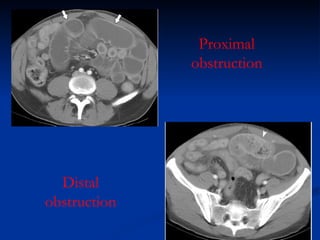

Proximal obstruction Distal obstruction

Intestinal obstruction SiteProximal s.b. obstruction Greather vomitimg and less intestinal distention than distal obstruction Colon obstruction Less fluid and electrolyte disturbance Large distension and perforation risk

Intestinal obstruction VomitingProximal obstruction produce profuse vomiting and little abdominal distension Distal obstruction is less frequent but feculent Initial phase byliary aspect Late phase feculent BUT

Intestinal obstruction Issensitive for diagnosing complete obstruction of the small bowel and determining the localization and cause of obstruction CT scan